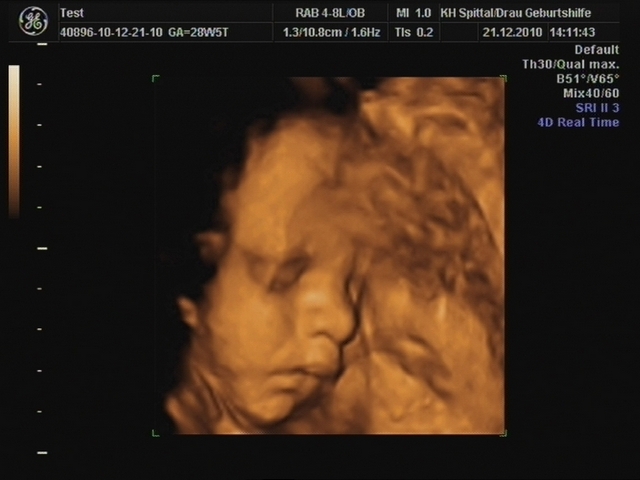

Zwischen der 20. und 22. Schwangerschaftswoche findet ein Organscreening statt. Dabei werden die verschiedenen Organe des Kindes mit einem hochauflösenden Ultraschallgerät genau untersucht. Hier können Fehlbildungen wie z.B. ein Herzfehler oder eine Lippen-Kiefer-Gaumenspalte frühzeitig diagnostiziert werden.